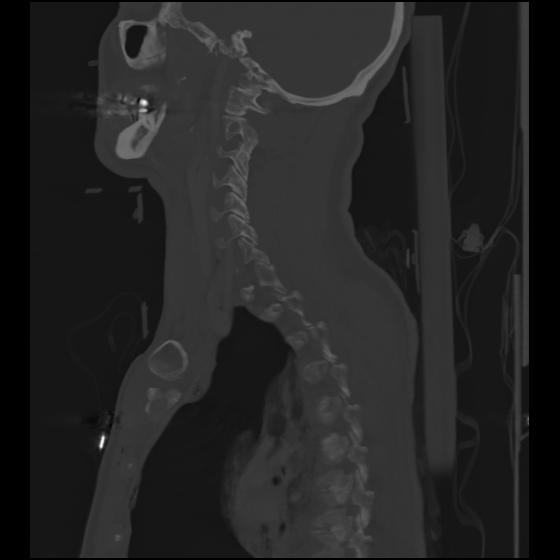

24 ANGIO,CE,Sag-MIP,5.000,ANGIO,Sag-MIP,